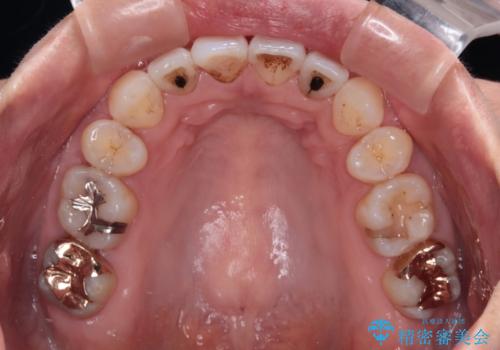

- 前方に飛び出した前歯を気にして来院された患者様です。

通常であれば上下左右の第一小臼歯4本を抜歯して口元の突出感を改善しますが、下顎前歯が1本欠損しており、上下の歯の数がアンバランスであるため、4本抜歯するかどうか悩むところでした。

上顎前歯はやや小さめで、下顎前歯はやや大きめであったため、上下左右4本を抜歯しても左右奥歯の咬み合わせは理想に近い状態を達成できると判断し、上下左右の第一小臼歯4本を抜歯し、ワイヤー装置にて矯正治療を行うこととしました。